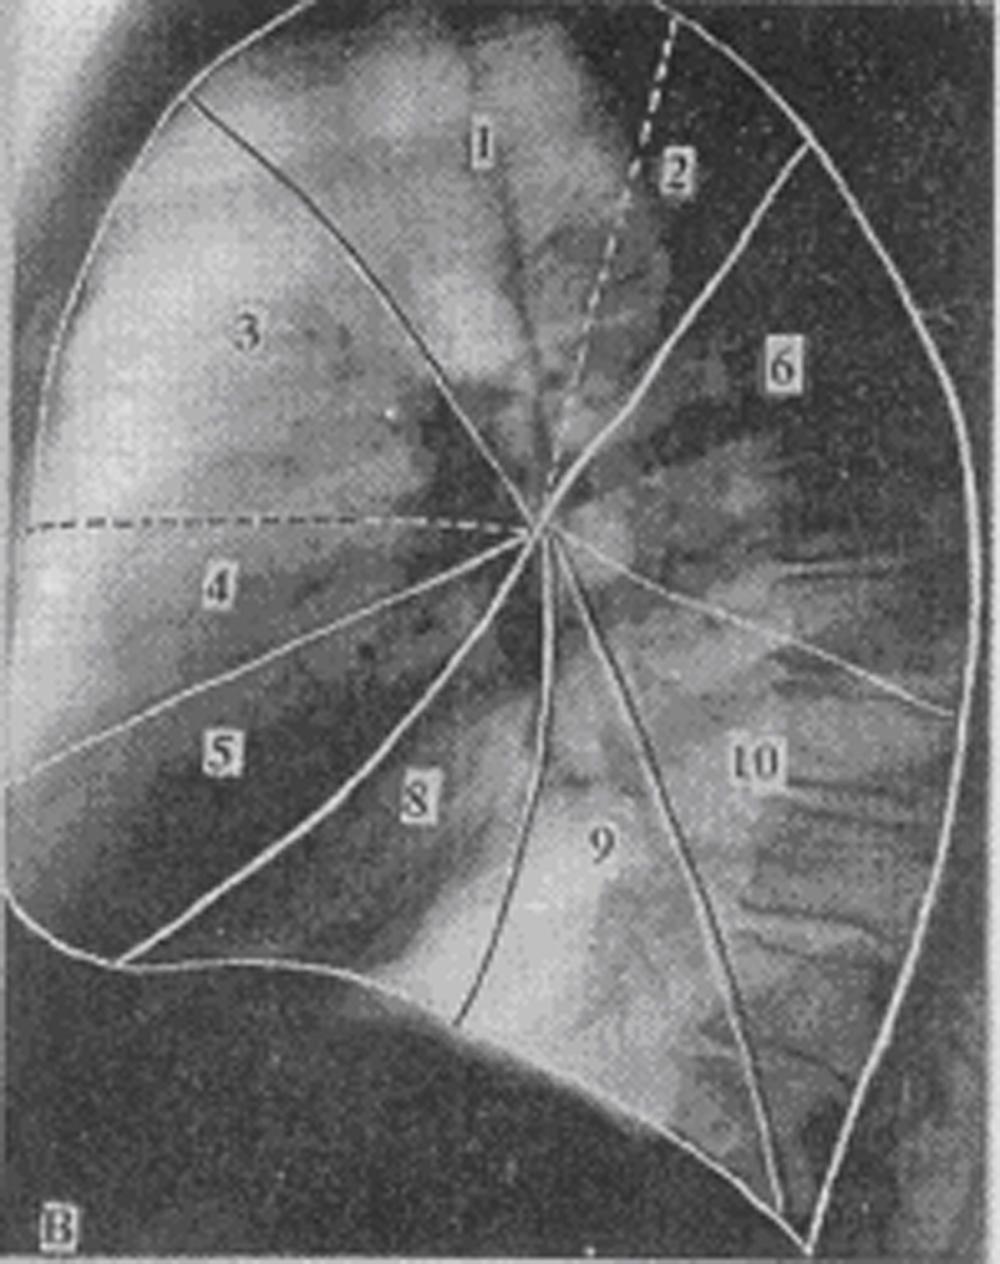

Анатомические изображения сегментов легких различных животных

Раздел: Другие животные